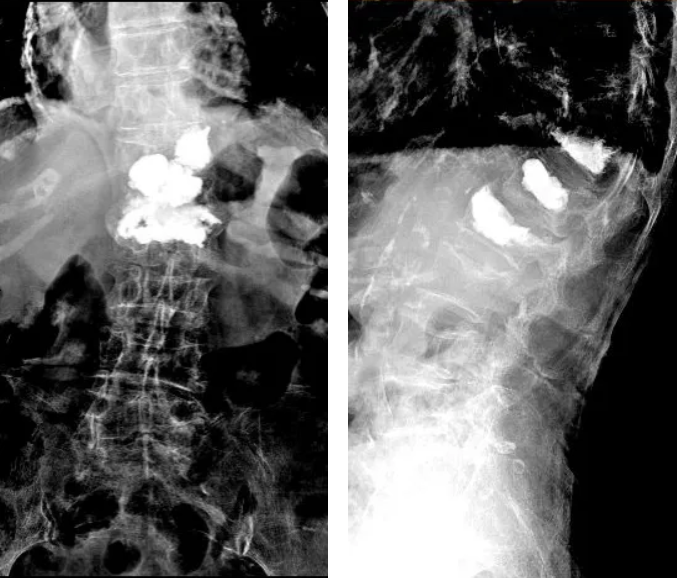

X线显示张奶奶多个节段的椎体都有不同程度的压缩骨折,其中胸12椎体压缩极为严重,腰1、腰2椎体有进行过经皮穿刺骨水泥成形术的征象,而磁共振检查结果显示,胸12椎体压缩骨折有偏新鲜的影像信号,这与张奶奶自己描述的疼痛位置和李永革主任医师团队体格检查的结果是相符的,所以李永革主任医师考虑患者再次发生了胸12椎体压缩骨折,才导致目前严重的疼痛。

入院后复查的X线片和磁共振